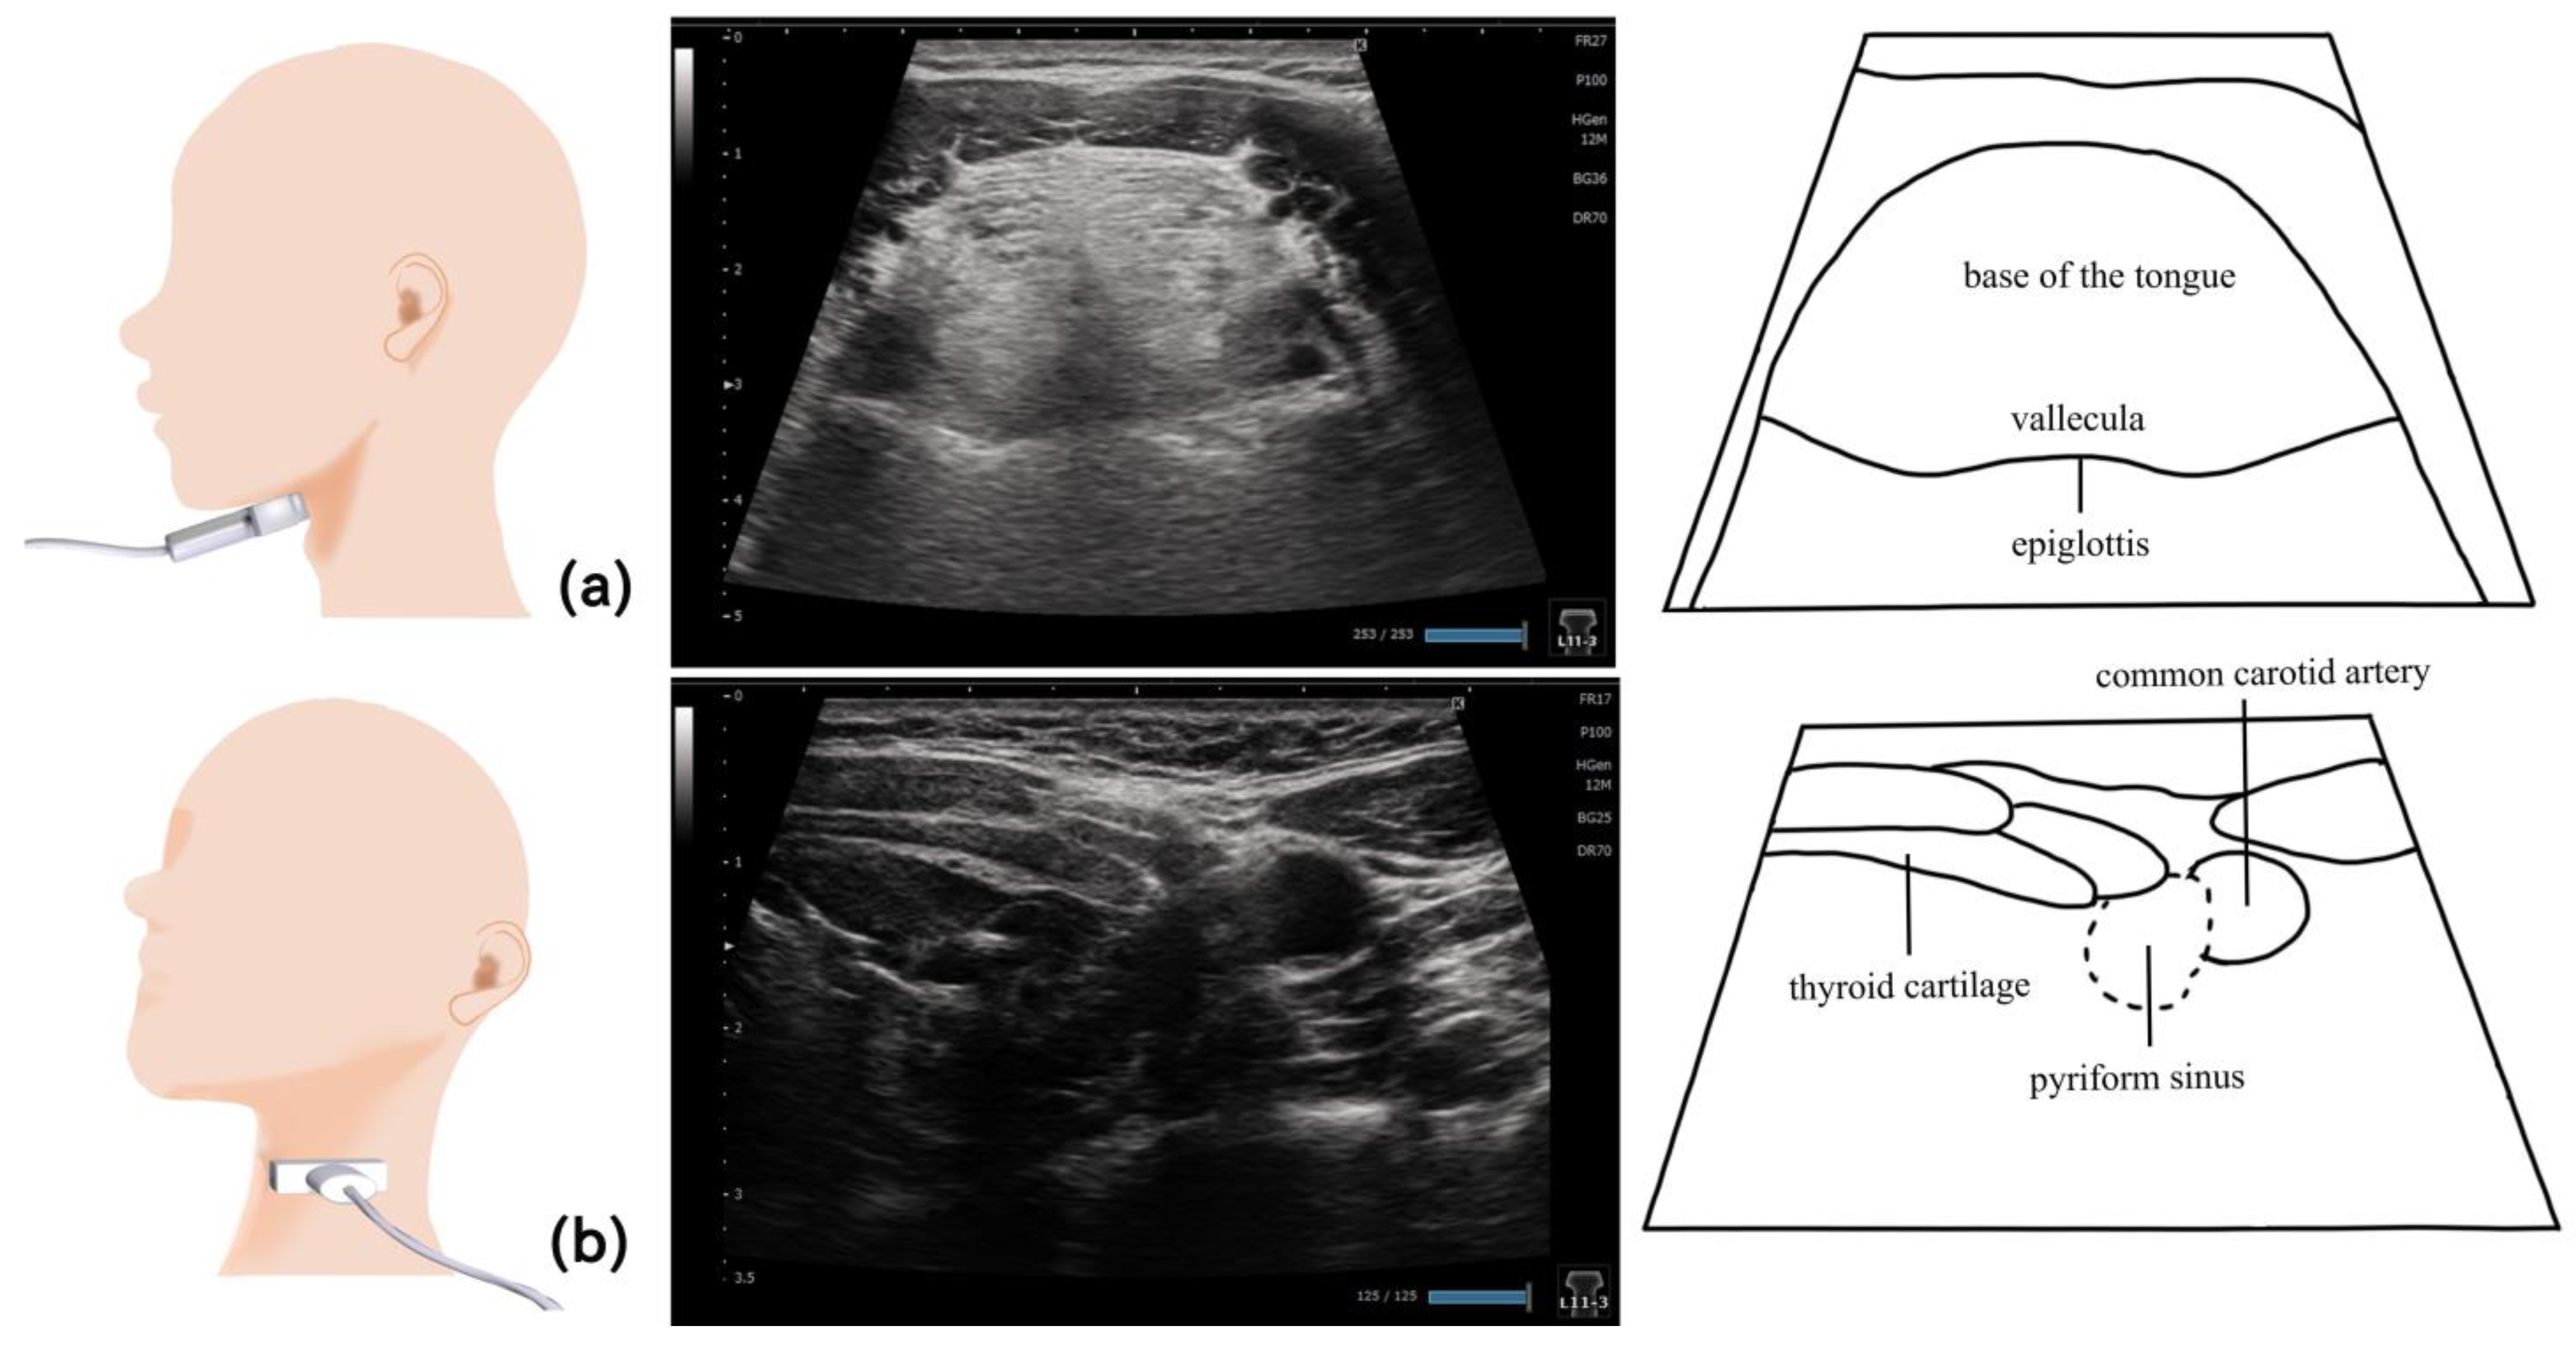

11. Pharynx (Figure 10 and Figure 11)

- Miura, Y.; Yabunaka, K.; Karube, M.; Tsutaoka, T.; Yoshida, M.; Matsumoto, M.; Nakagami, G.; Kamakura, Y.; Sugama, J.; Sanada, H. Establishing a Methodology for Ultrasound Evaluation of Pharyngeal Residue in the Pyriform Sinus and Epiglottic Vallecula. Respir. Care 2020, 65, 304–313. [Google Scholar] [CrossRef]

- Miura, Y.; Nakagami, G.; Yabunaka, K.; Tohara, H.; Hara, K.; Noguchi, H.; Mori, T.; Sanada, H. Detecting pharyngeal post-swallow residue by ultrasound examination: A case series. Med. Ultrason. 2016, 18, 288–293. [Google Scholar] [CrossRef]

- Miura, Y.; Nakagami, G.; Yabunaka, K.; Tohara, H.; Murayama, R.; Noguchi, H.; Mori, T.; Sanada, H. Method for detection of aspiration based on B-mode video ultrasonography. Radiol. Phys. Technol. 2014, 7, 290–295. [Google Scholar] [CrossRef]